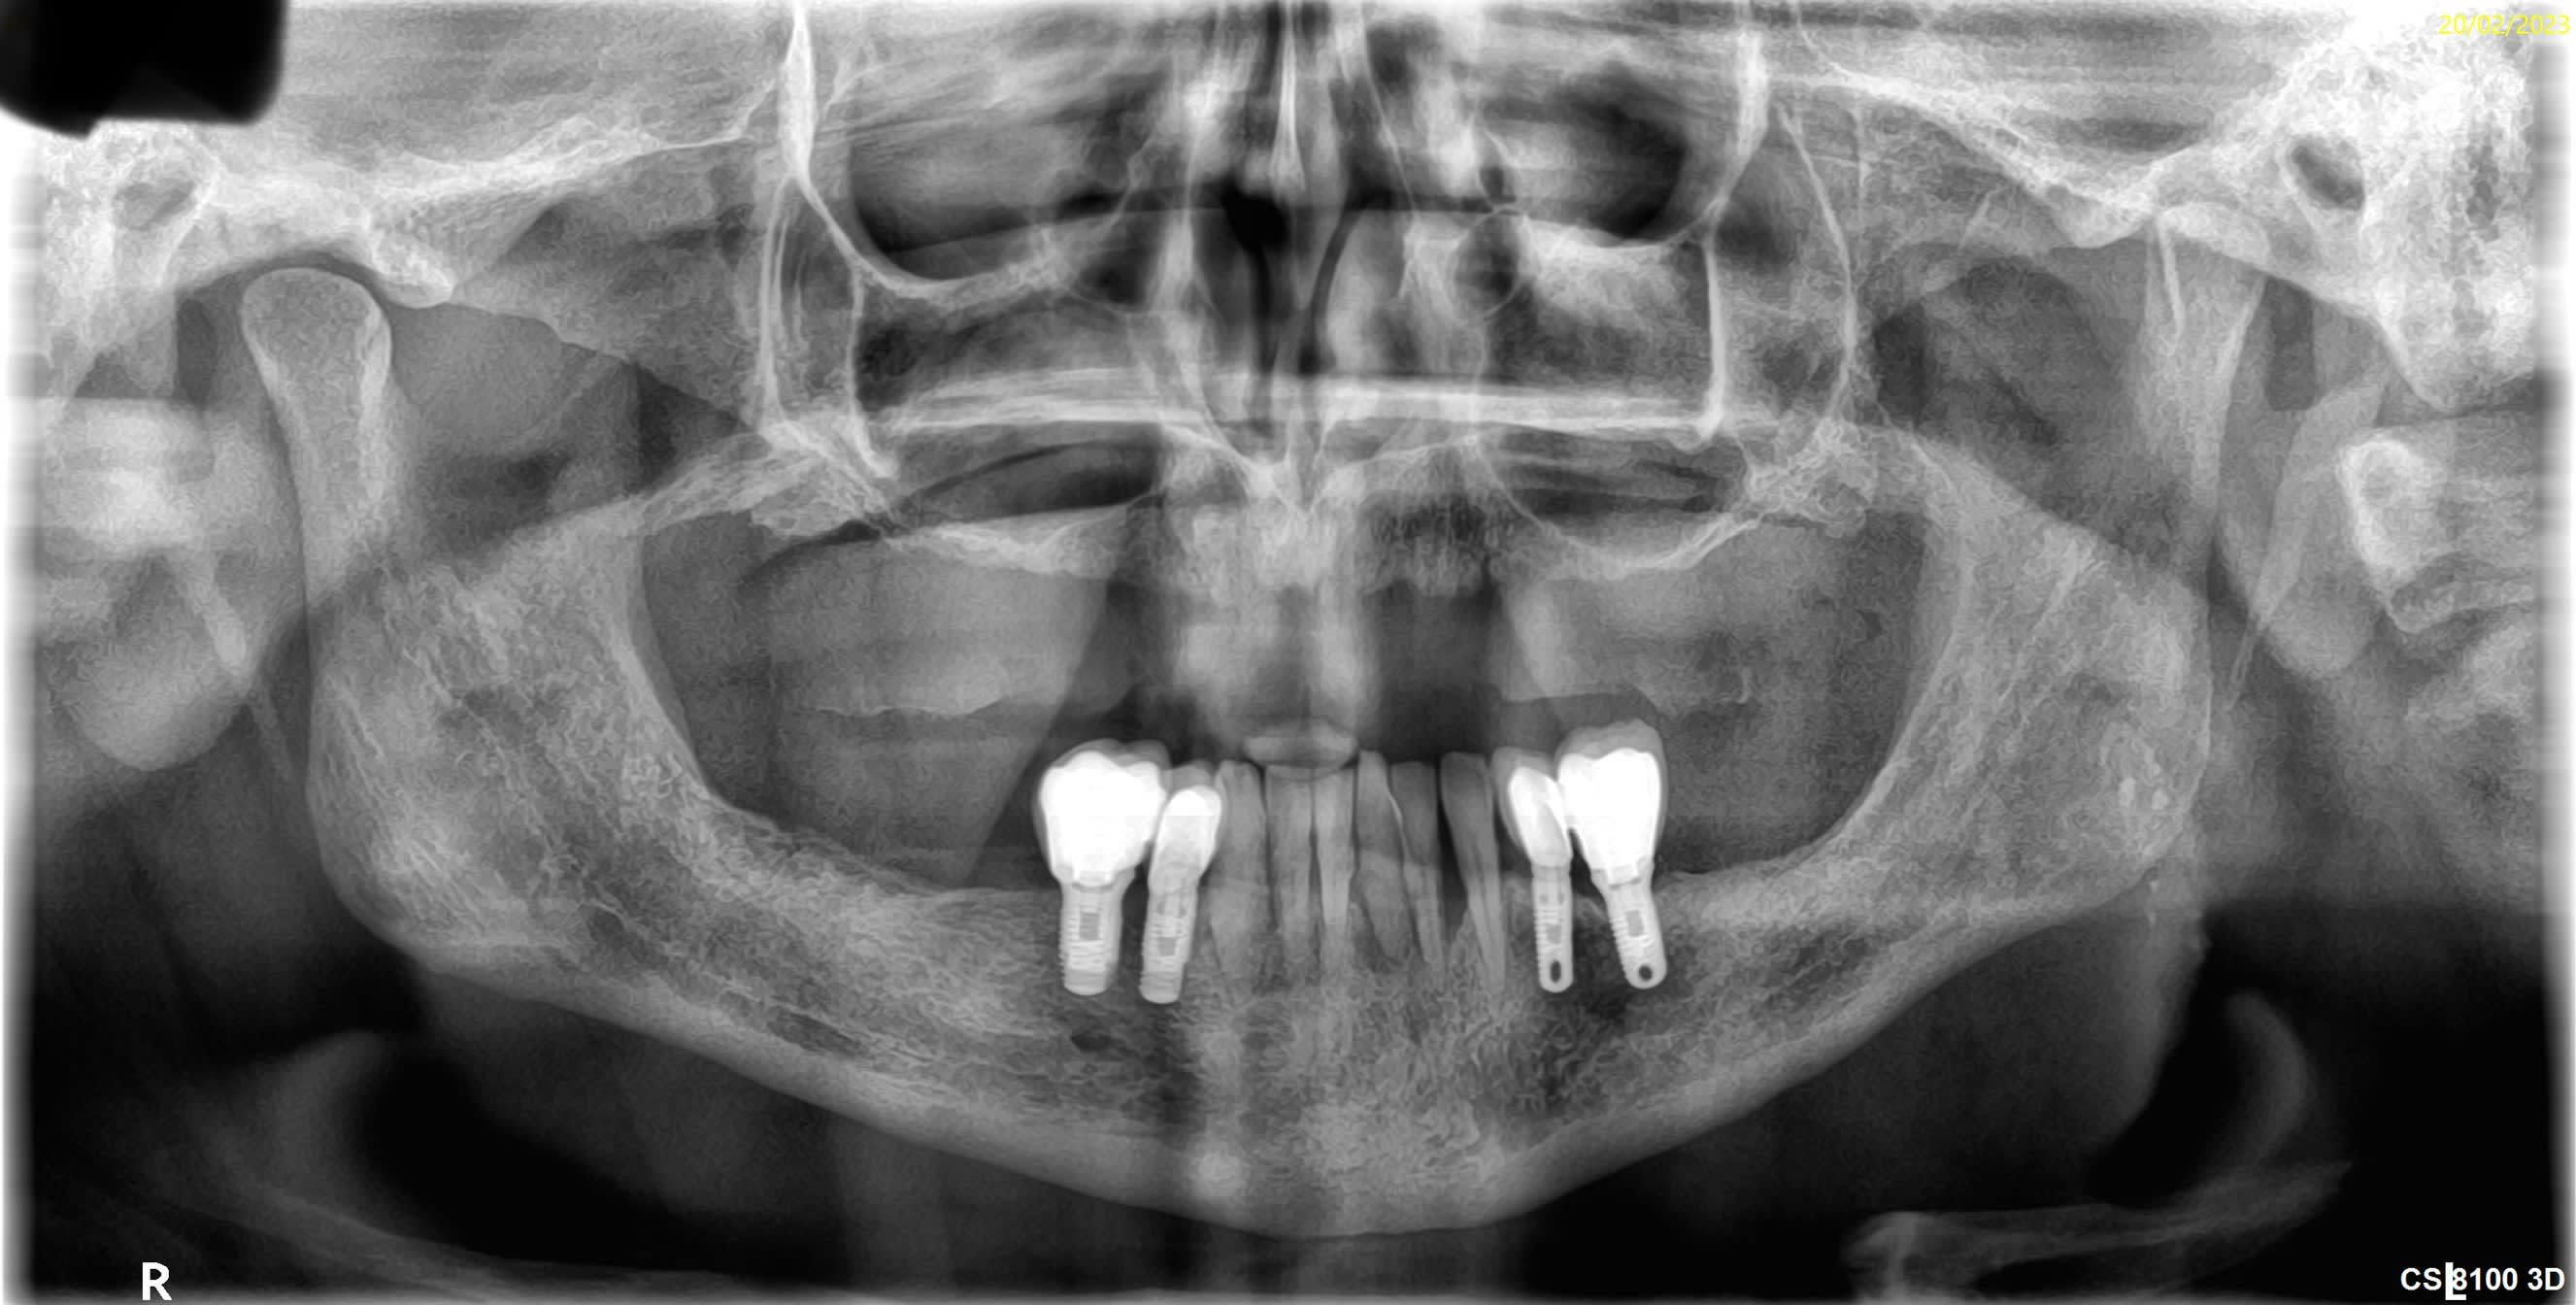

Bonsoir pourriez vous m’aider pour la marque de ces implants je pense à du zimmer tsv pour les implants en position de 4…je pense que les implants distaux sont des zimmer aussi car posé par le même praticien mais j’ai l’impression que ce sont des tissus level est ce que la connectique est identique?

Pour les premo c’est des TSV, et les molaires des AdVent zimmer pour les 2….

Connexion différente, hex interne pour les TSV, octogonale comme des straumann pour les AdVent